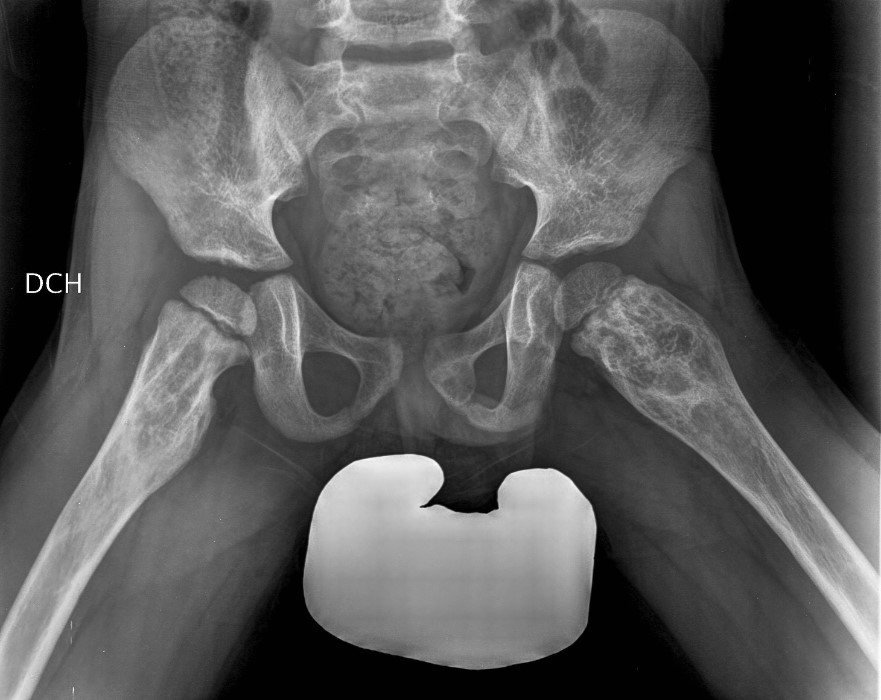

Mientras se exploraba se detectó una mancha café con leche de gran tamaño (10 × 5 cm) y bordes irregulares en la región lumbar izquierda y una de menor dimensión (4 × 3 cm) en la región lumbar central (Fig. 1). La lesión cutánea estaba presente, según los padres, desde el nacimiento. No presentaba prurito ni otras lesiones cutáneas. Desarrollo psicomotor y neurológico normal. Sin ningún antecedente personal ni familiar de interés, salvo una cojera ocasional desde hacía unos meses, sin recordar un traumatismo. Se realizó una radiografía de pelvis y miembros inferiores en la que se observó una displasia fibrosa (Fig. 2). Para completar el estudio y descartar la existencia de displasia fibrosa en otros huesos, se realizó una serie ósea en la que también se observó afectación en el cráneo, a nivel frontal, aunque asintomática. Ante la clínica y las pruebas complementarias, sospechamos un síndrome de McCune-Albright, que fue confirmado con el estudio genético.

Figura 2. Radiografía de pelvis y miembros inferiores. Displasia fibrosa

Radiografía de pelvis y miembros inferiores. Displasia fibrosa